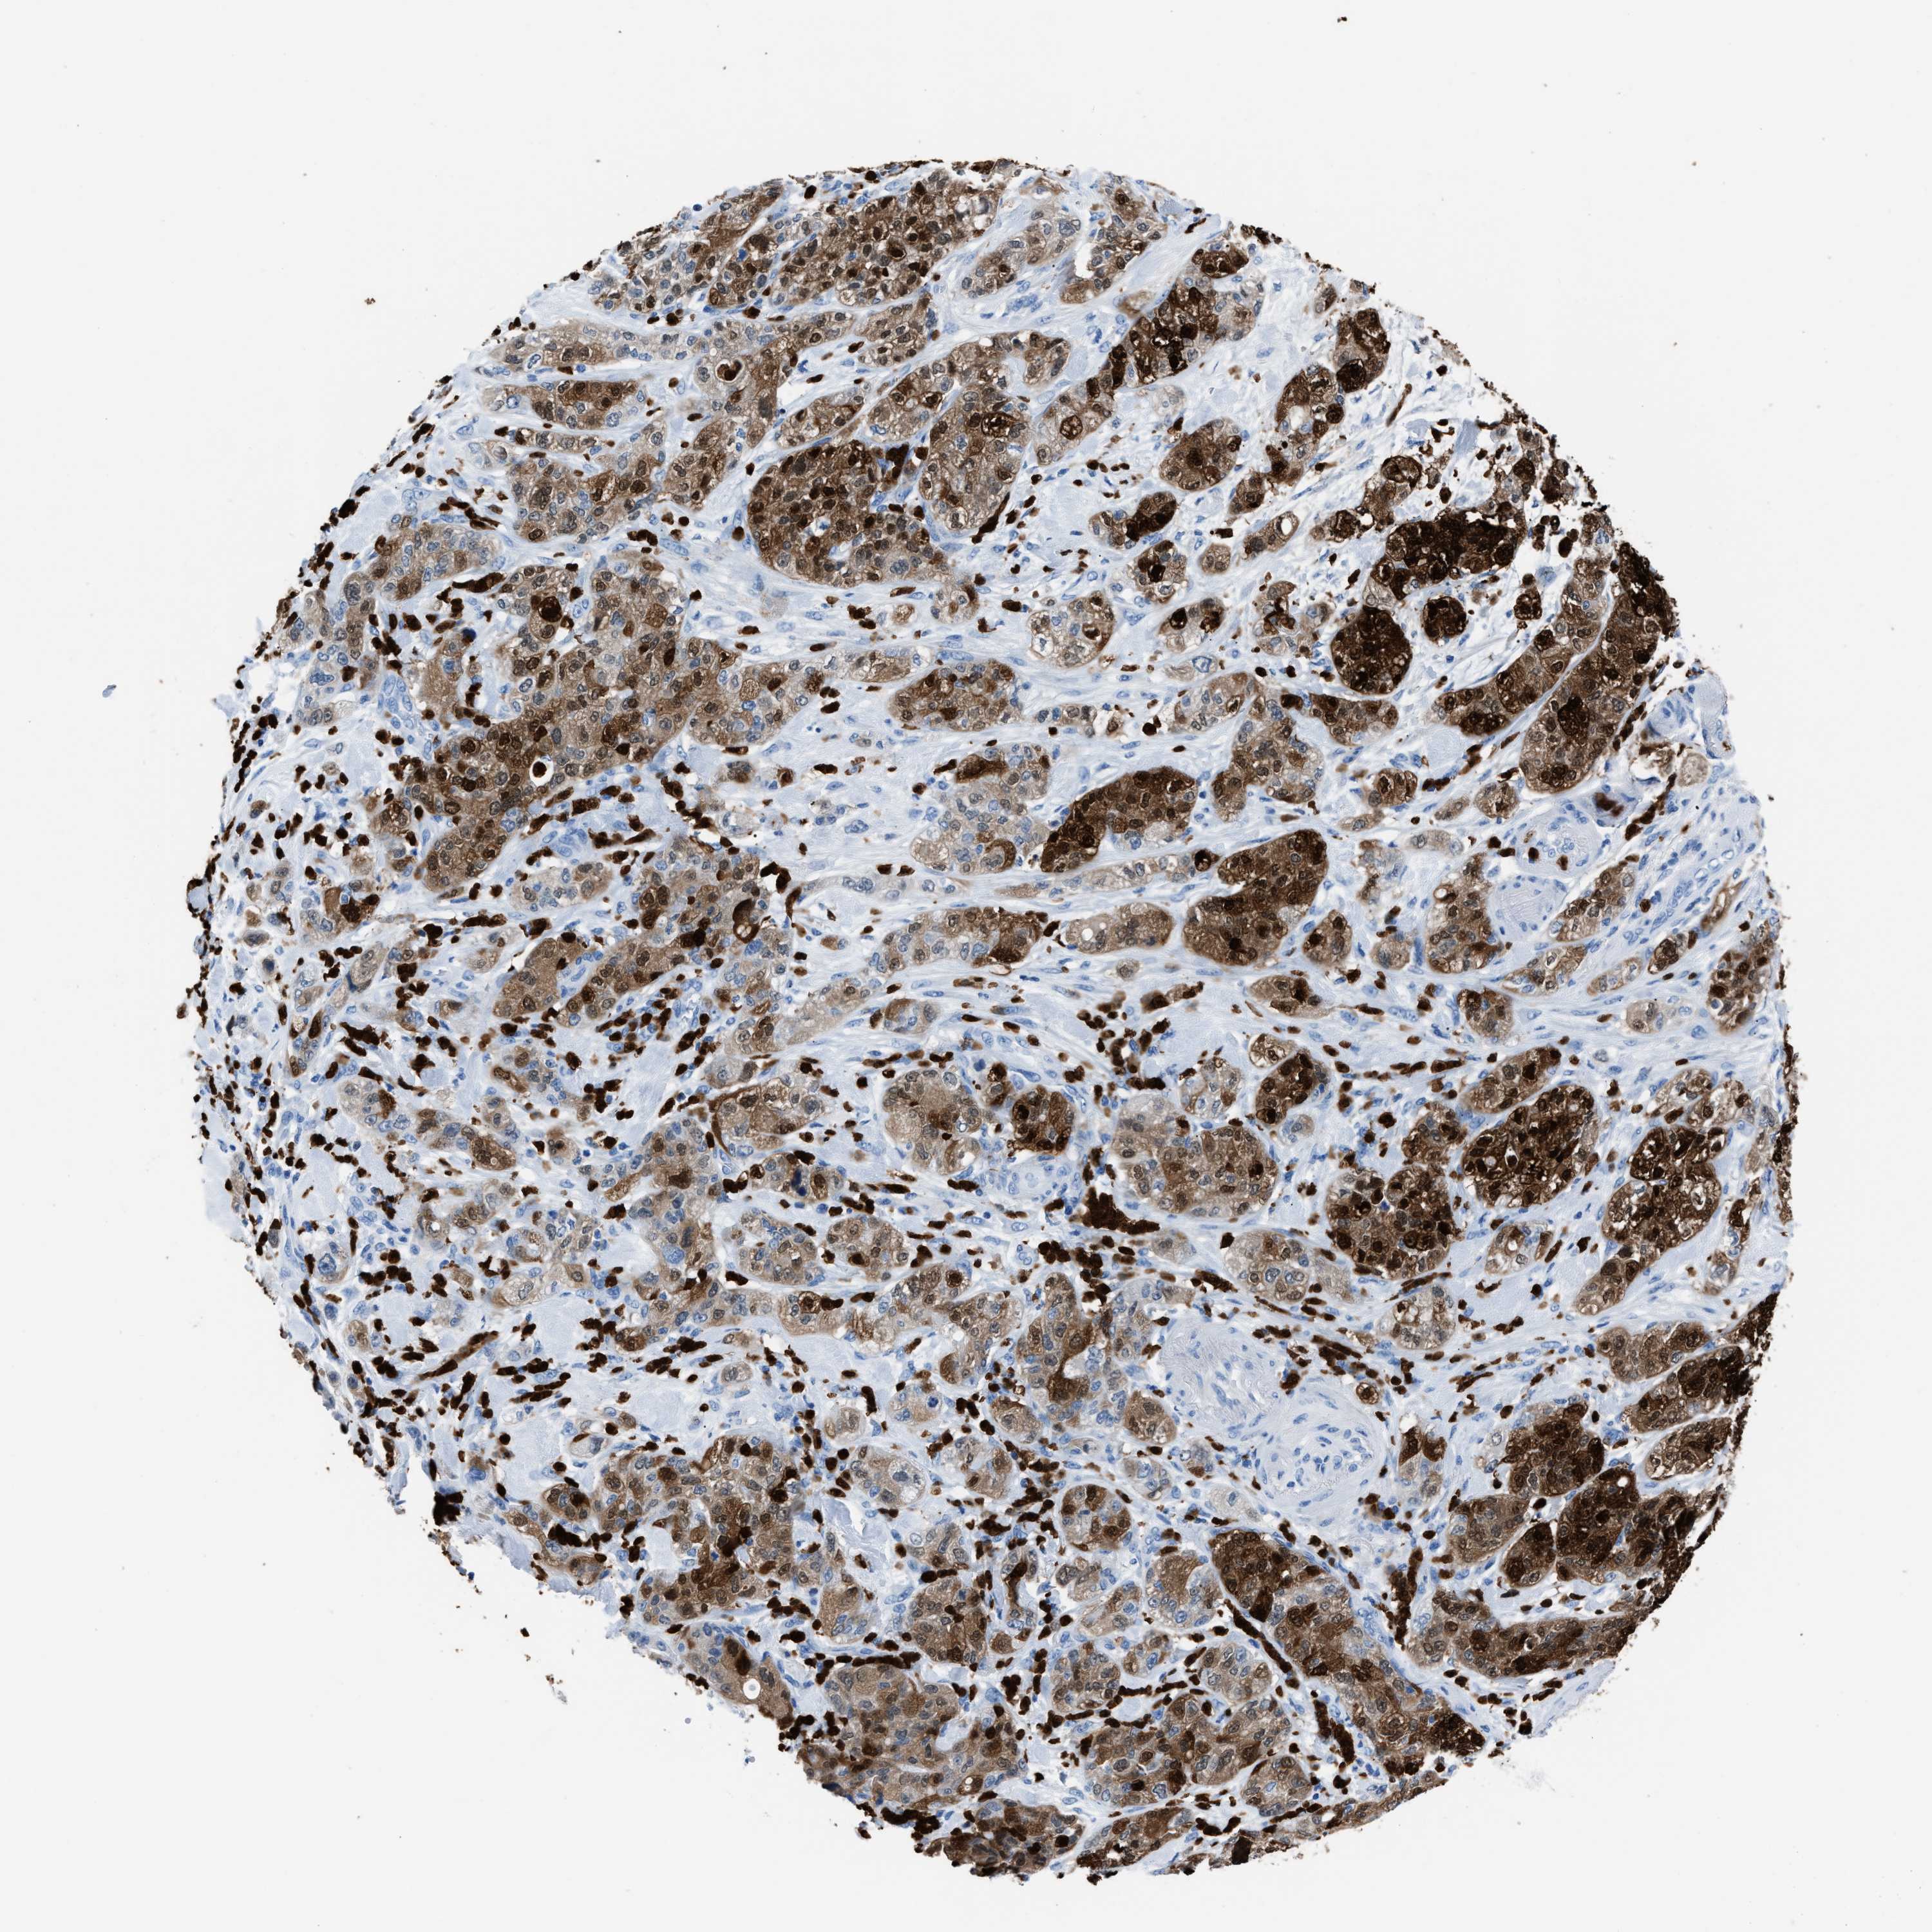

PANCREATIC CANCER - Protein expressioni

A mouse-over function shows sample information and annotation data. Click on an image to view it in a full screen mode. Samples can be filtered based on level of antibody staining by selecting one or several of the following categories: high, medium, low and not detected. The assay and annotation is described here.

Antibody stainingi

Antibody staining in the annotated cell types in the current human tissue is reported as not detected, low, medium, or high, based on conventional immunohistochemistry profiling in selected tissues. This score is based on the combination of the staining intensity and fraction of stained cells.

Each image is clickable and will lead to virtual microscopy that enables deeper exploration of all samples and also displays staining intensity scores, fraction scores and subcellular localization as well as patient and tissue information for each sample.

Antibody HPA019502

Staining

High

Medium

Low

Not detected

Intensity

Strong

Moderate

Weak

Negative

Quantity

>75%

75%-25%

<25%

None

Location

Nuclear

Cytoplasmic/membranous

Cytoplasmic/membranous,nuclear

Adenocarcinoma, NOS